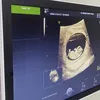

Lewat kanal Youtube SULE Family, Sule mengabadikan foto USG janin di dalam kandungan Nathalie saat periksa.